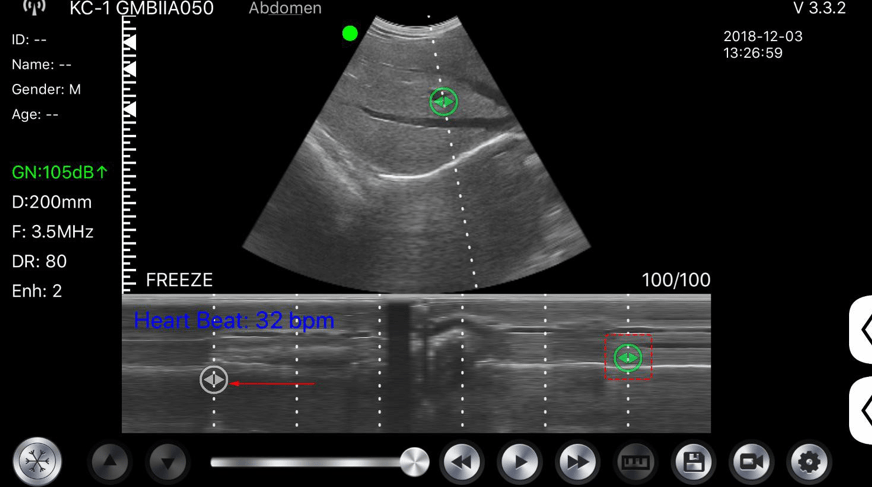

C10MT 3.5-5.0Mhz Convex B&W, Colour Portable Ultrasound.

The new C10MT Colour Doppler Hand Held Ultrasound probes with 128 element 24 frame per second frame rate gives real imaging performance for any application.

• Display mode: B, B/M, colour, PW, PDI

• B+M Heart Rate, Time, Distance